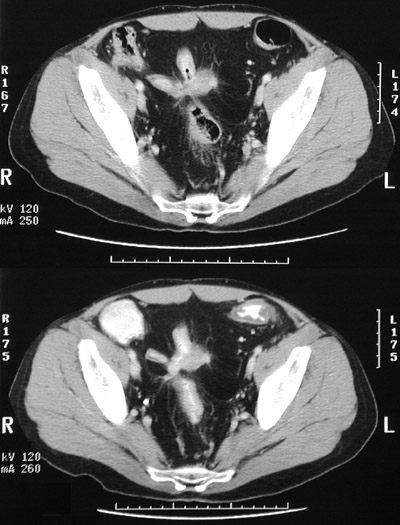

An abdominal CT scan is performed:

3.3 How does this explain the initial findings above?